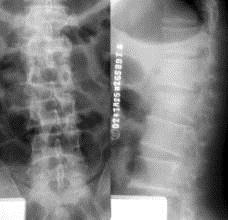

病历摘要: 患者×××,男性,21岁,不慎从3米高处坠落,双足着地,出现双足跟肿胀疼痛,腰痛不能站立。查体:腰1棘突有压痛和叩击痛,双足足跟部肿胀,触痛(...

问题 病历摘要: 患者×××,男性,21岁,不慎从3米高处坠落,双足着地,出现双足跟肿胀疼痛,腰痛不能站立。查体:腰1棘突有压痛和叩击痛,双足足跟部肿胀,触痛(+),双下肢感觉正常,双足伸足母、伸趾正常,双膝关节伸屈正常。 关于脊髓损伤的治疗原则以下叙述哪些是正确的?